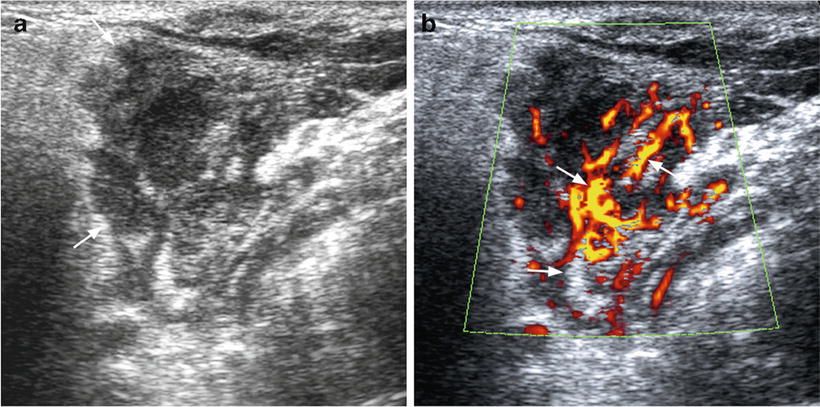

Colon Cancer Ultrasound Radiology Case Radiopaedia Org from prod-images-static.radiopaedia.org To see whether the cancer has spread, some or all of the lymph nodes are removed and checked for cancerous cells. We prospectively studied 19 patients referred to the institut gustave. It can be used with a fine needle aspiration test or core biopsy test to accurately direct the tip of the needle into the lump. If this lump is of concern then a biopsy would be the next step. They deliver blood from your heart to your brain. Head and neck cancers include cancers in: However, an ultrasound can tell if a lymph node has an abnormal architecture possibly because it is infiltrated by tumor. Sonography, when performed by an experienced examiner, can be used for evaluation of many pathologies in the head and neck area.

While it can't diagnose cancer, it can detect the abnormal tissues that may possibly be cancerous. Ultrasound is often one of the first line tests in the detection of cancer. For neck or thyroid mass see ent. Lymph nodes are part of the lymphatic system, which helps to protect us from infection and disease. Some of the indications for thyroid or neck ultrasound are thyroid nodules, goiter, thyroid cancer and other neck masses. Ultrasound imaging is a noninvasive medical test that helps physicians diagnose and treat medical conditions. Part of the throat (cancers of the oropharynx and tonsils, nasopharynx and hypopharynx) the nose or sinuses (nasal and sinus cancer) the salivary glands. Ultrasound guidance is used to perform thyroid biopsies and improves the diagnostic accuracy of fine needle biopsy. Sonography has an accuracy rate of about … Fna might also be used in patients whose cancer has been treated by surgery and/or radiation therapy , to help find out if a neck mass in the treated area is scar tissue or if it's a return (recurrence) of the cancer. If the person has a lump in the neck, an fna can show if the mass is from cancer spread. It can be used with a fine needle aspiration test or core biopsy test to accurately direct the tip of the needle into the lump. It can detect abnormal tissues, growths, and cysts and give a suspicion of cancer based on how those images look.